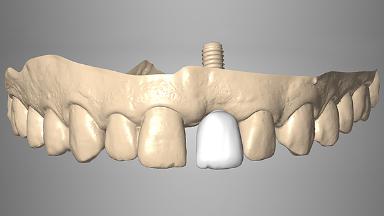

Immediate Loading of an Anterior Implant with a Prefabricated Crown

A fully digital workflow for a patient with adequate bone but soft tissue defects is outlined in this case. Key features include: Use of the CAD software’s mirroring feature to create the digital diagnostic wax-up, a CAD/CAM custom zirconia abutment and PMMA provisional crown, connective-tissue grafting performed at the time of implant placement, and modification of the provisional crown to shape the emergence profile and change the position of the labial mucosal margin to better match the contralateral tooth.